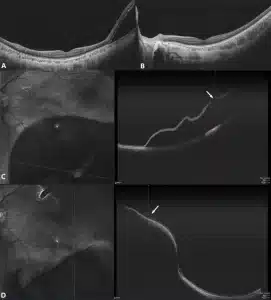

Comparison of OCTA before and after treatment for a rhegmatogenous retinal detachment. A and C. Presurgery images illustrating macular on status and most of SRF below the inferotemporal atrophic hole (white arrow). B and D. Three-day postoperative images demonstrating the hole (white arrow) is draped accurately over the buckle, a little SRF around peripheral inferior retina and the macula is not involved